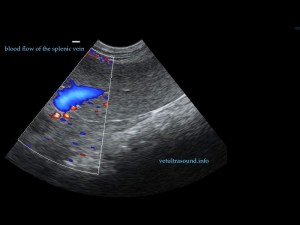

Ευρήματα: Η κεφαλή του σπλήνα βρέθηκε μετατοπισμένη ( στραμένη προς τα οπίσθια άκρα) με υποκαψικές περιοχές υποηχογένειας, χωρίς αιμάτωση (pic 1,2,3). Το τμήμα αυτό του σπλήνα ήταν διογκωμένο σε σχέση με το υπόλοιπο όργανο και το μεσεντέριο λίπος που το περιέβαλε ήταν έντονα υπερηχογενές. Στο συγκεκριμένο σημείο του σπλήνα τα μεγάλα αγγεία δεν είχαν ροή αίματος κατά τον έλεγχο με έγχρωμο Doppler (pic3). Αντίθετα το σώμα και η ουρά του οργάνου είχαν φυσιολογική αιμάτωση και μέγεθος (pic 4,5).

pic2